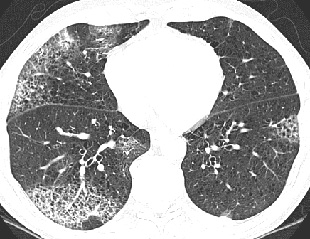

CT/HRCT

• Centrilobular micronodules (rare tree-in-bud) predominantly upper lobes

• Mosaic perfusion

• Lucent lung, small vessels in lucent lung